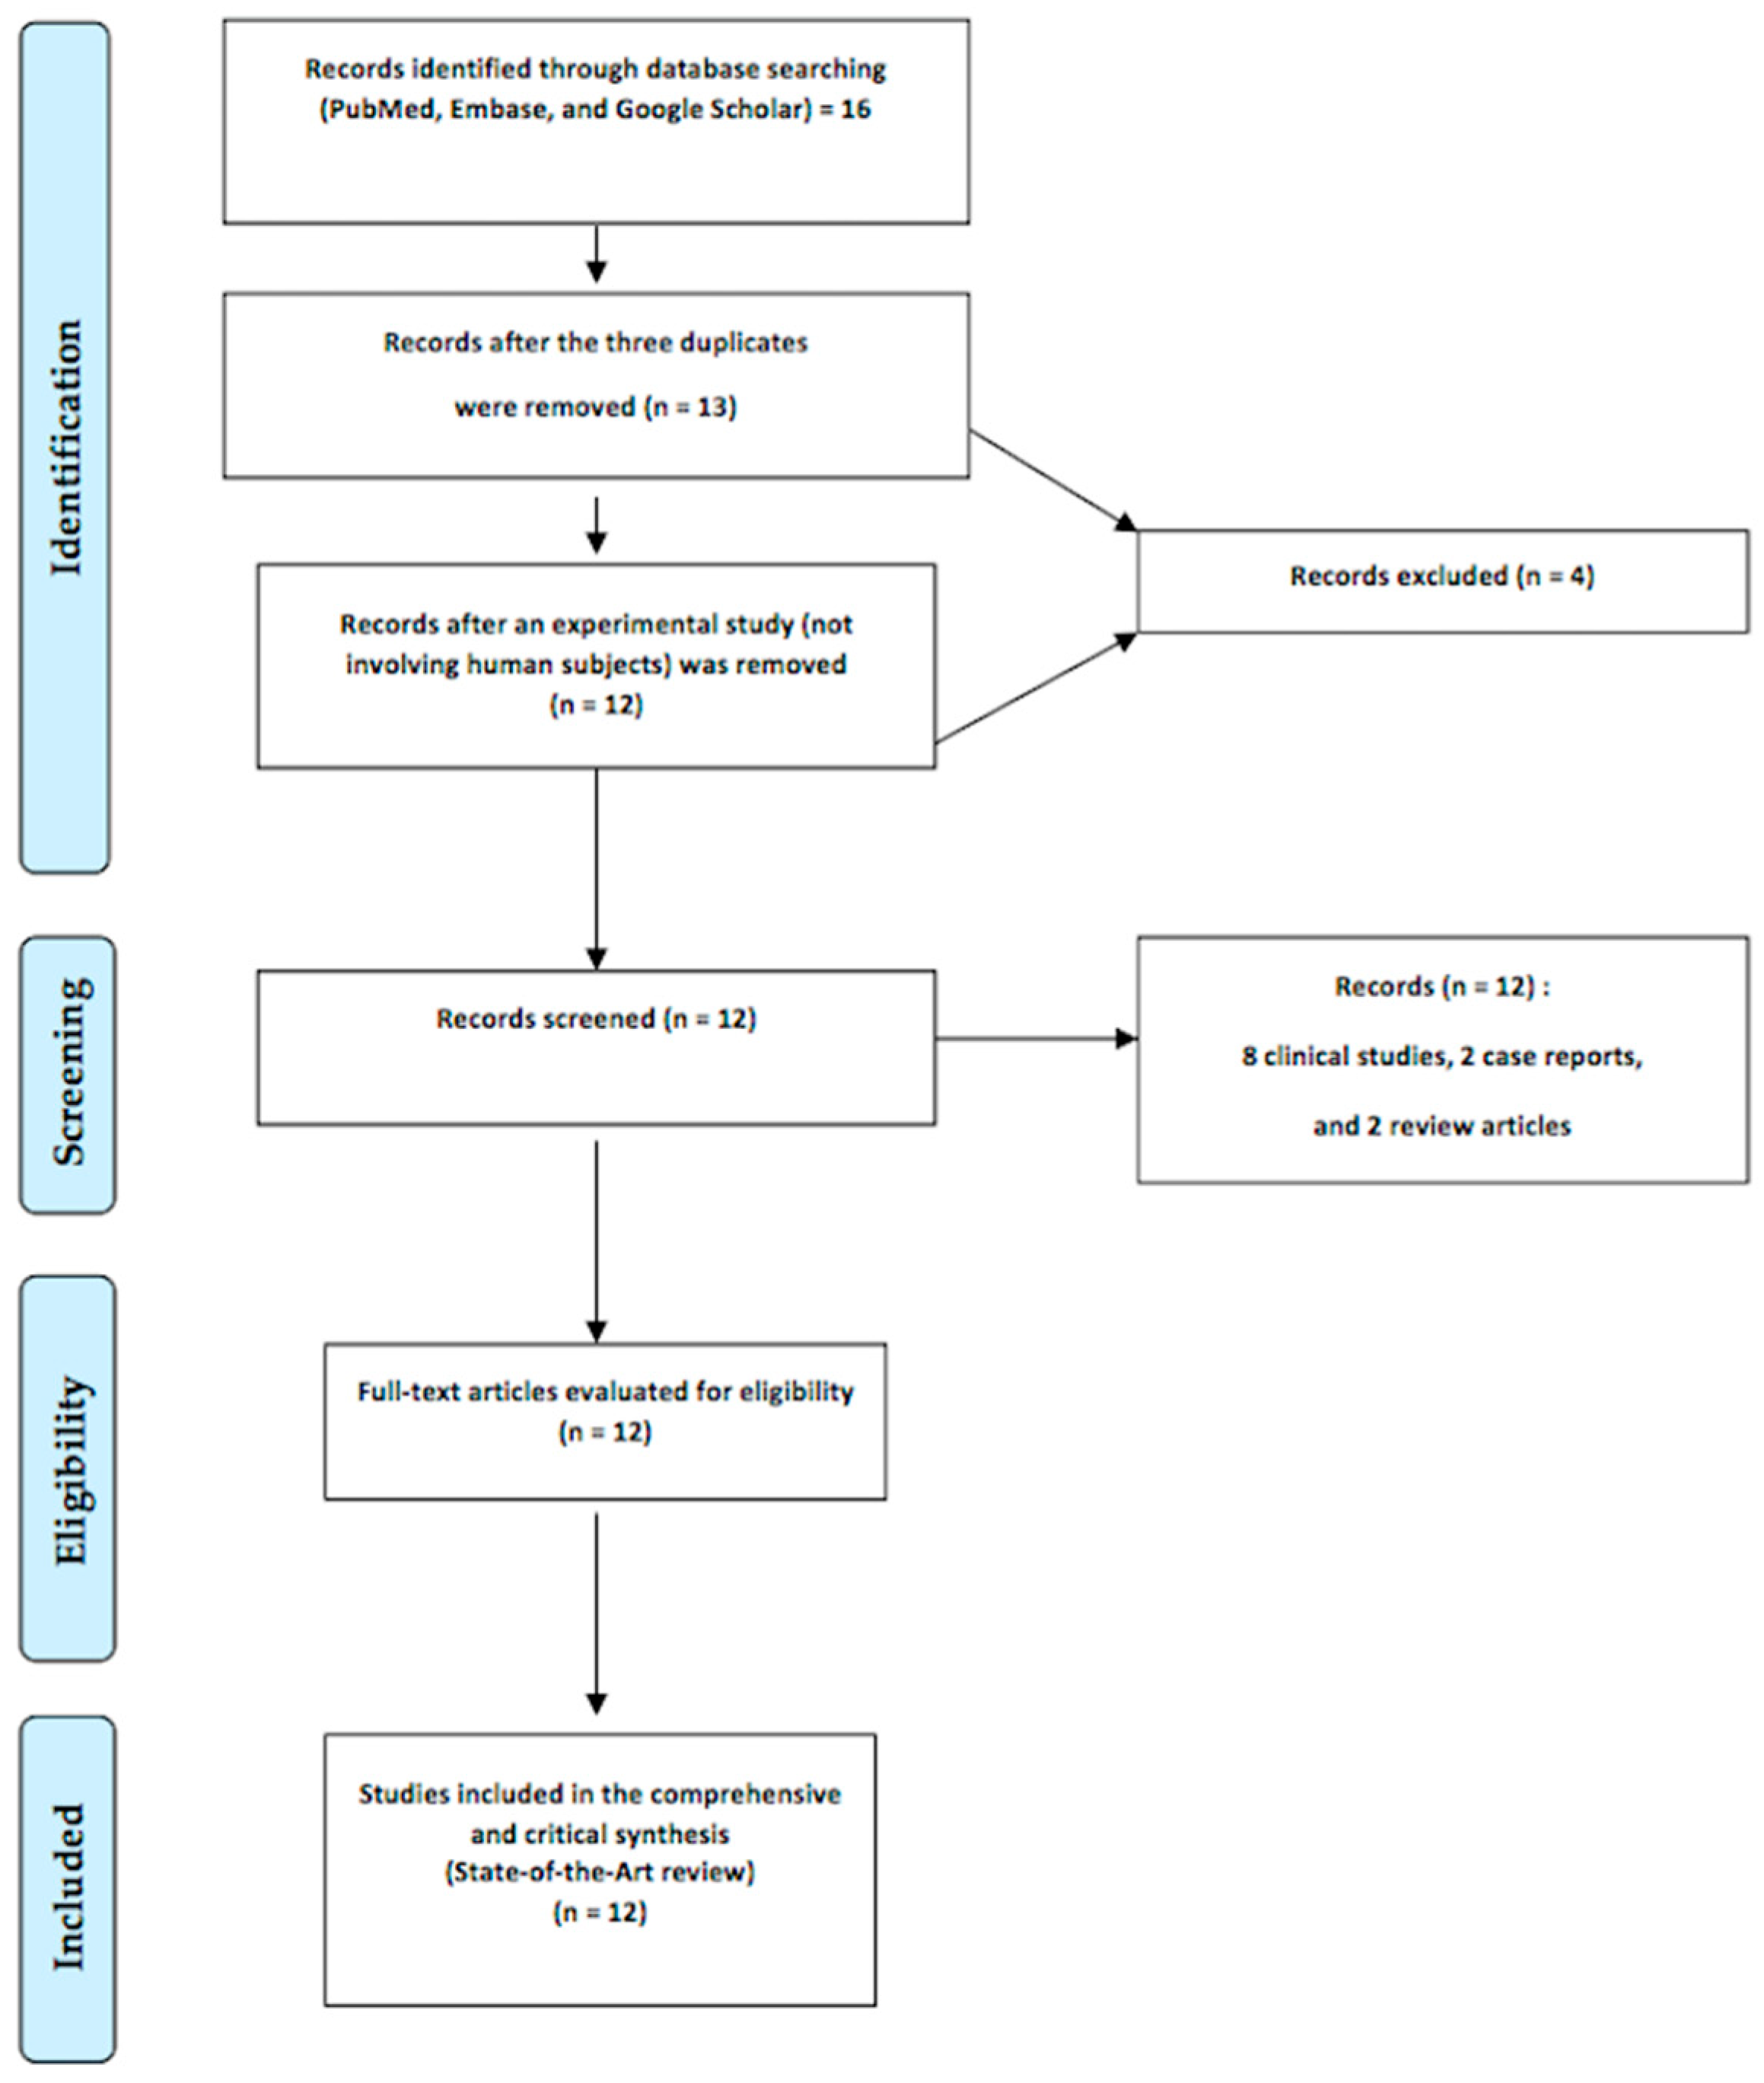

1.3. The Aim of this Study

2.4. Literature Review